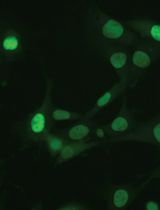

Metastasis depends on a gene program expressed by the tumor microenvironment upon TGF-beta stimulation. CRC (Colorectal cancer) cell lines did not induce robust stromal TGF-beta responses when injected into nude mice as shown by lack of p-SMAD2 accumulation in tumor-associated stromal cells. To enforce high TGF-beta signaling in xenografts, we engineered CRC cell lines to secrete active TGF-beta. Subcutaneous tumors obtained from HT29-M6TGF-β, KM12L4aTGF-β cells and SW48TGF-β cells contained abundant p-SMAD2+ stromal cells.

Figure 1. p-SMAD2 staining (arrowhead) in liver metastasis generated after intrasplenic injection of CRC cells. E: epithelial cells, Str: stromal cells. Scale bars = 10 μm